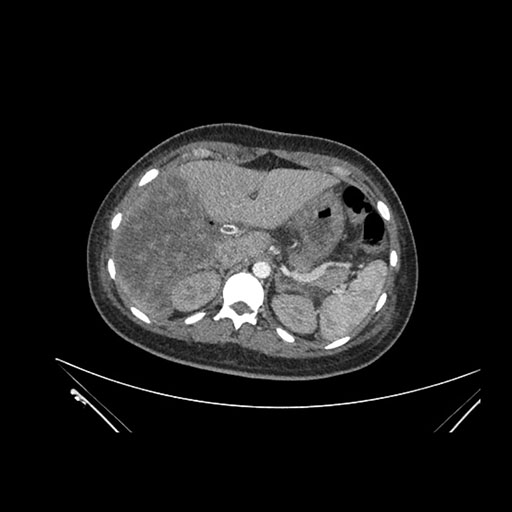

Axial Arterial